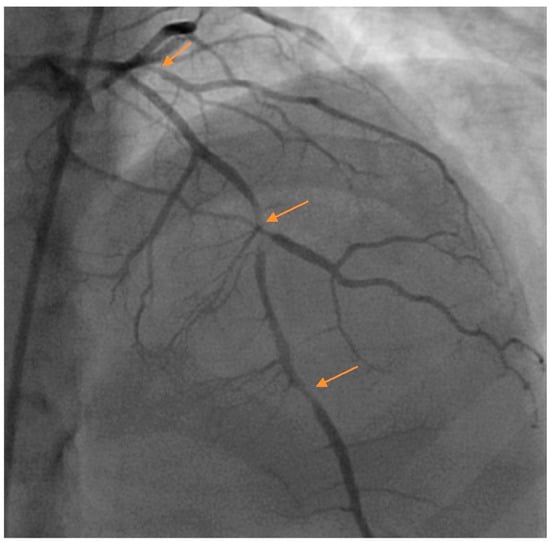

Pregnancy-related SCAD accounts for approximately 10% of SCAD cases [2], with most cases occurring in the immediate postpartum period [18]. The presentation is often comparatively more severe with a greater proportion of patients presenting with ST elevation myocardial infarction, ventricular fibrillation, proximal and multivessel SCAD [19] (Figure 1). Pregnancy related SCAD is associated with fewer extracoronary vascular abnormalities and possibly a lower risk of recurrence [18]. Estrogen and progesterone surges during pregnancy can cause medial degeneration of the arterial wall from decreased collagen synthesis and increased media mucopolysaccharide content, causing weakening of the vessel wall [20]. Whether or not other mechanisms are implicated is not well established. Patients suffering from pregnancy related SCAD are generally recommended to avoid future pregnancies. Table 2 lists several risk factors and suggested actions to take for patients with SCAD.

Figure 1.

Multivessel spontaneous coronary artery dissection (SCAD) in a postpartum female presenting with acute coronary syndrome (ACS). Arrows denote areas of dissection. Images courtesy of Steven Cohen, M.D.